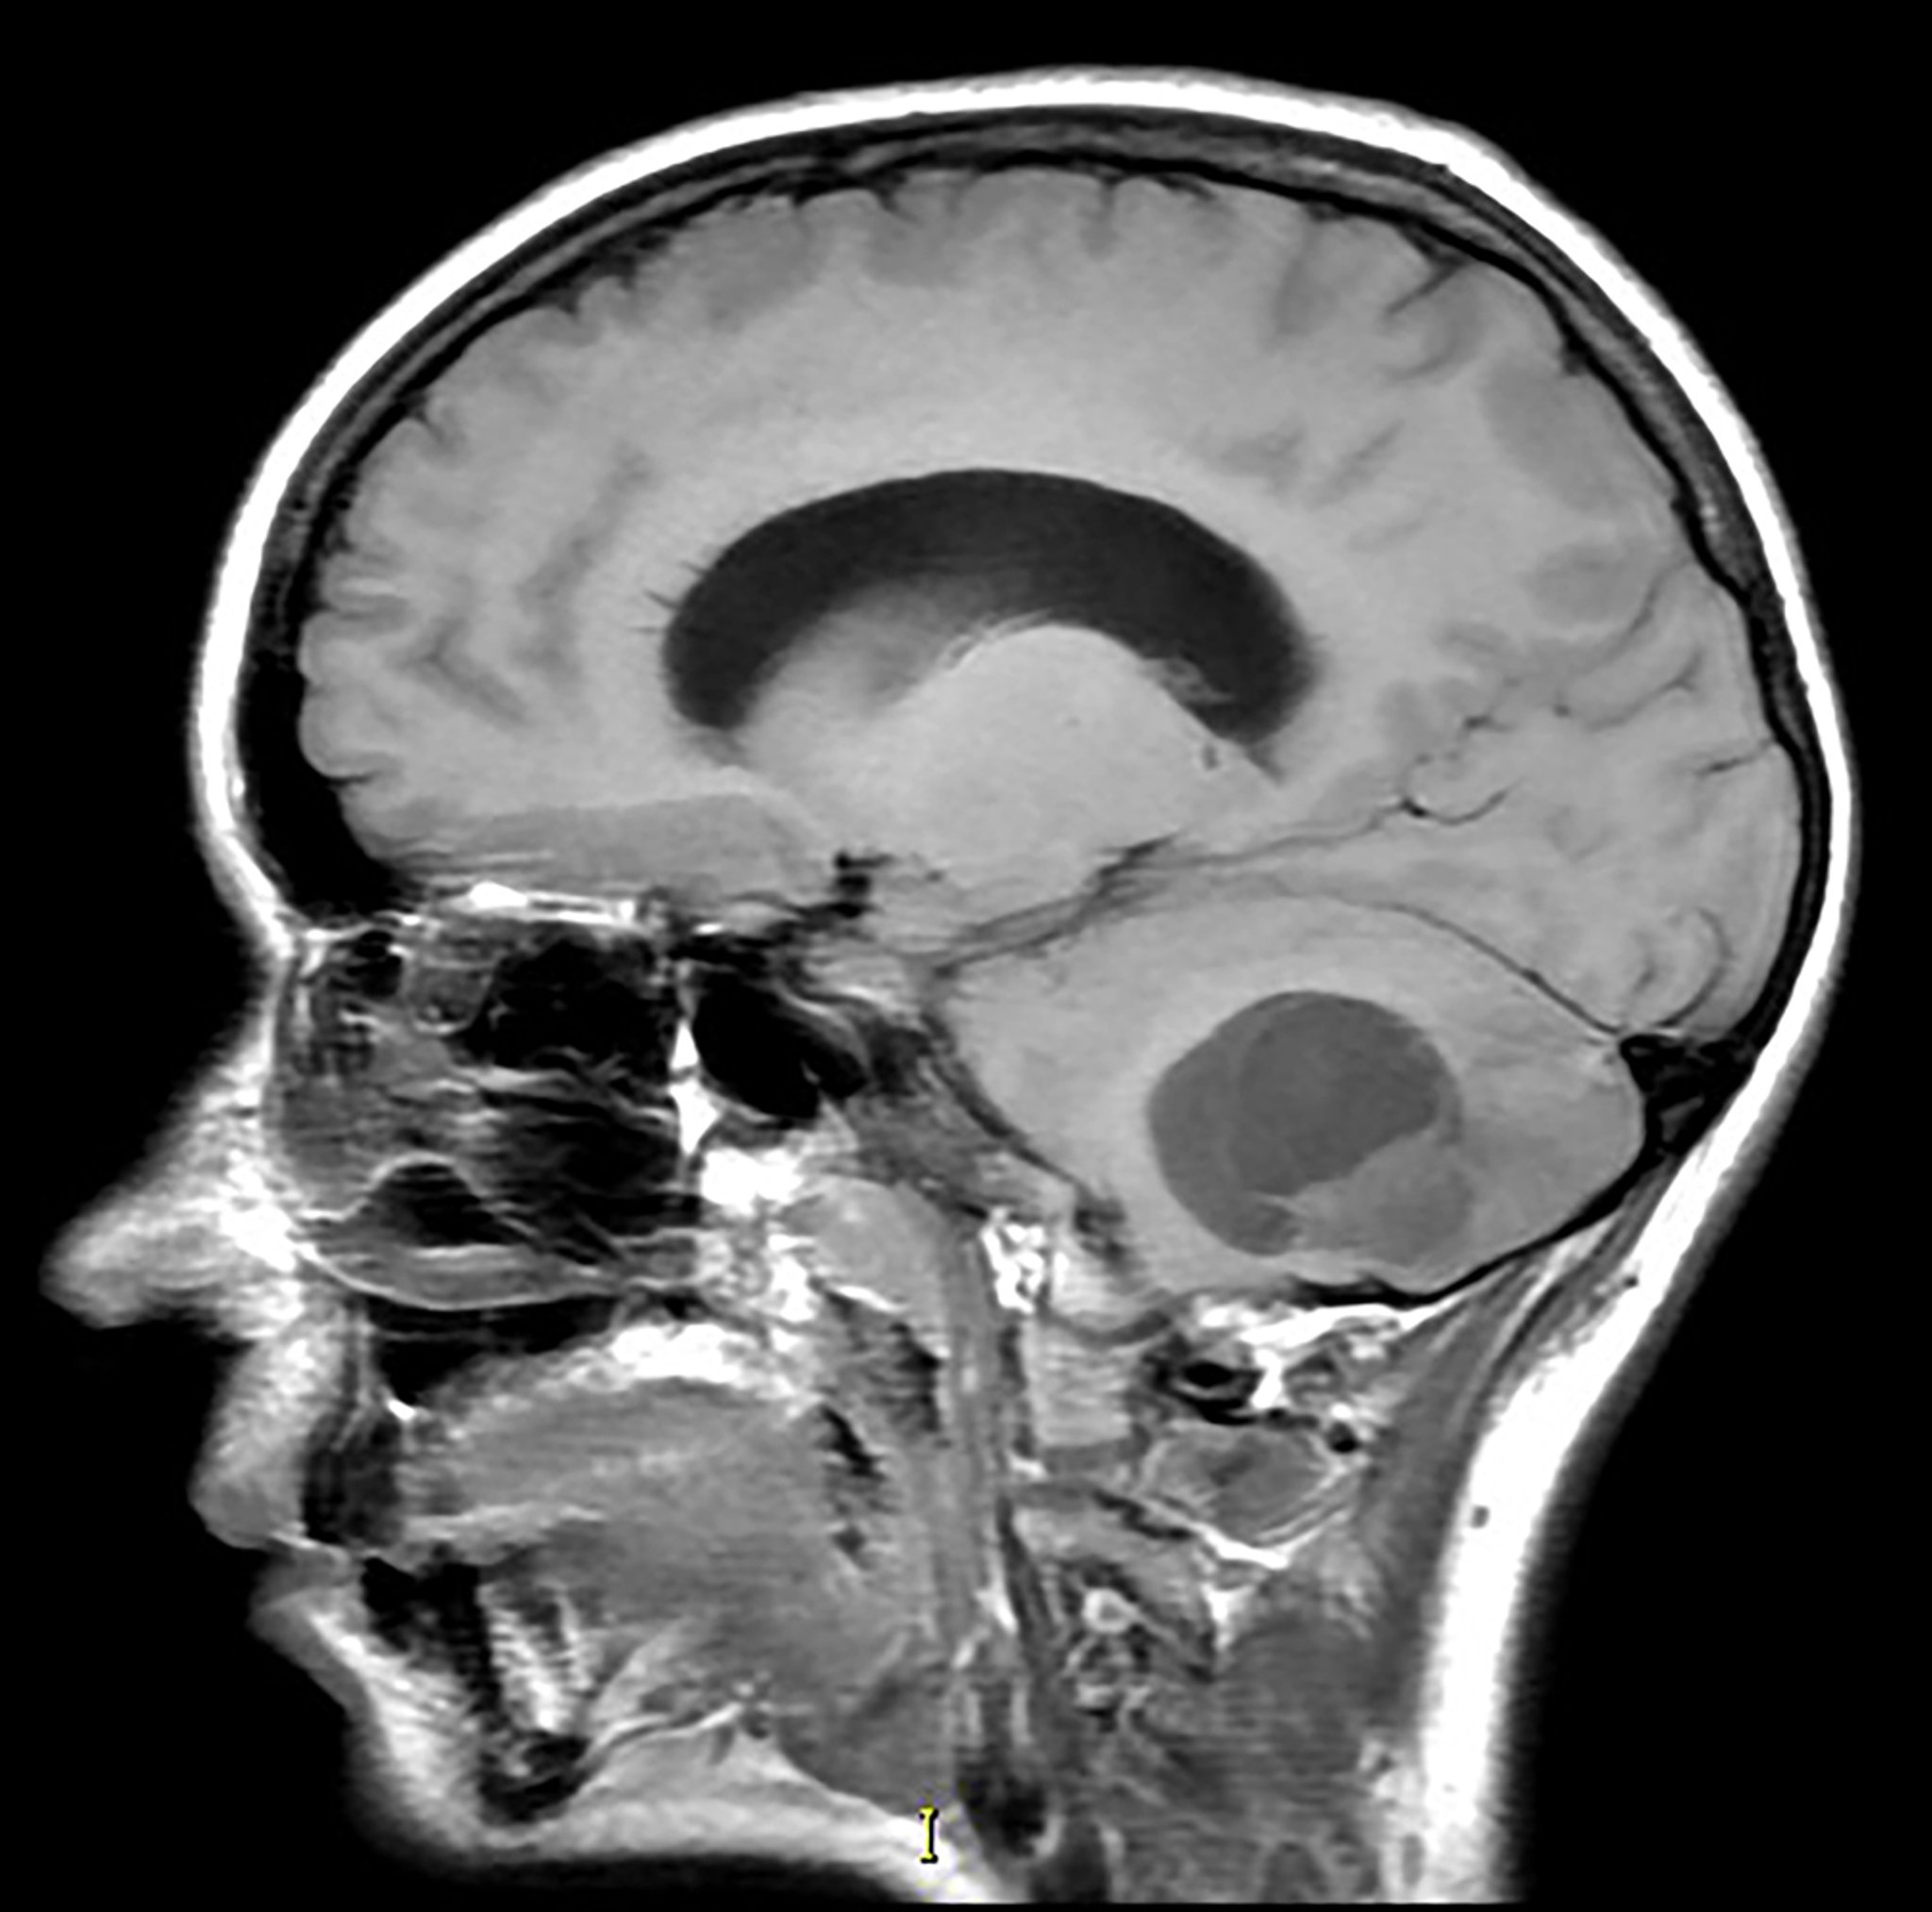

Cerebellar Hemangioblastoma (MRI)

This sagittal T1-weighted magnetic resonance image without contrast shows a partially cystic and solid mass in the inferior cerebellum with associated mass effect. This is the most common appearance of a hemangioblastoma. This tumor is seen with increased frequency in patients with von Hippel-Lindau syndrome.